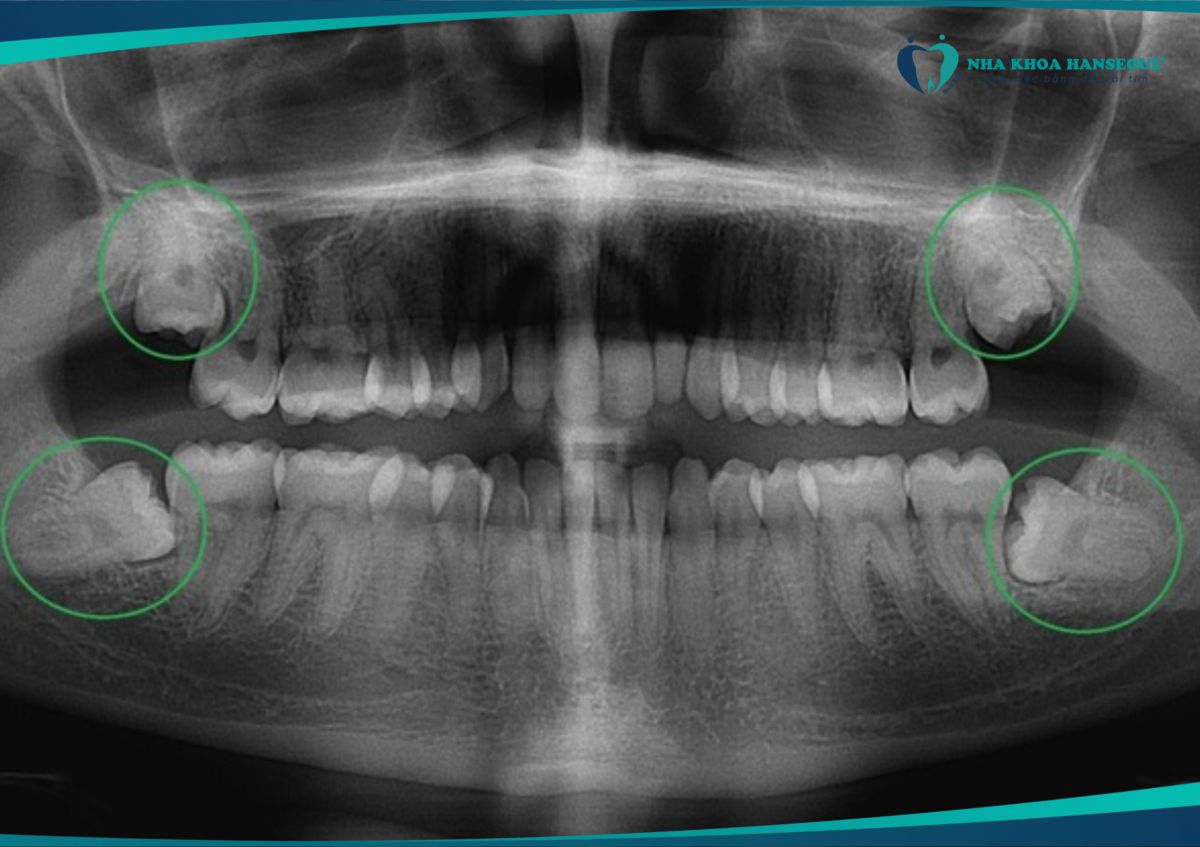

Vì vậy, ngay cả khi răng số 8 không đau, bạn vẫn nên chụp X-quang để kiểm tra vị trí mọc và nghe tư vấn từ nha sĩ.

Răng số 8 mọc không đau vẫn có thể gây ra các biến chứng có hại nên cần được loại bỏ sớm

8 Răng mọc lệch, mọc ngầm

- Nếu chụp X-quang thấy răng khôn mọc xiên, đâm ngang hoặc nằm ngầm dưới nướu, nha sĩ sẽ khuyên nhổ sớm.